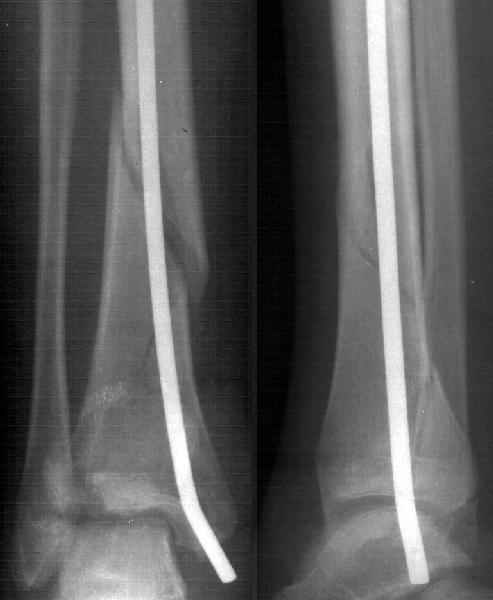

A female 14 y.o. sustained a spiral fracture of the distal tibia 1.5 years ago (Image 1). She was treated elsewhere by closed retrograde nailing with a thin nail (Image 2). The nail was removed after healing.

Image 2